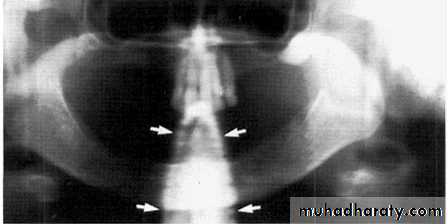

Ghost of spinal column

due to slumping

White tapered opacity in middle of image

Slumped; note the white spine shadow in

midline